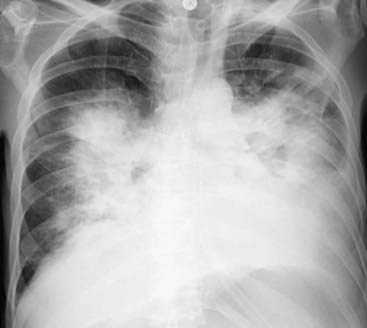

Figure 9-16 Bat-wing pattern of pulmonary edema.

The radiographic findings of pulmonary alveolar edema include fluffy, indistinct, patchy airspace densities frequently centrally located and sparing the outer third of the lung. This is called the bat-wing (angel-wing) or butterfly pattern, and it suggests pulmonary edema versus other airspace diseases such as pneumonia. The patterns of cardiogenic and noncardiogenic pulmonary edema overlap considerably, but the absence of pleural effusions, absence of fluid in the fissures, and the normal-sized heart favor a noncardiogenic cause in this case. The patient was in septic shock from an overwhelming urinary tract infection.